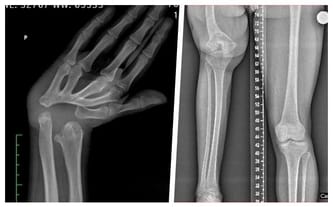

Nie znam innego życia – urodziłam się z krótszą prawą nogą i zdeformowaną dłonią w prawej ręce. Mam niedorozwój kości udowej i zanik stawu biodrowego. Przez to noga jest zdeformowana, a do operacji moja ręka nie spełniała swoich funkcji – nie byłam nawet w stanie nic nią utrzymać.

Z butem o podwyższonej podeszwie poruszałam się do ukończenia 10 lat. W tamtym czasie różnica między nogami wynosiła 16 cm. Obecnie to aż 23 centymetry… Poruszam się z pomocą ortezy. Kolejni lekarze odmawiali mi dalszych operacji. Powrócił ból, który utrudnia mi poruszanie się co teraz, kiedy opiekuję się synkiem, jest mi szczególnie potrzebne.